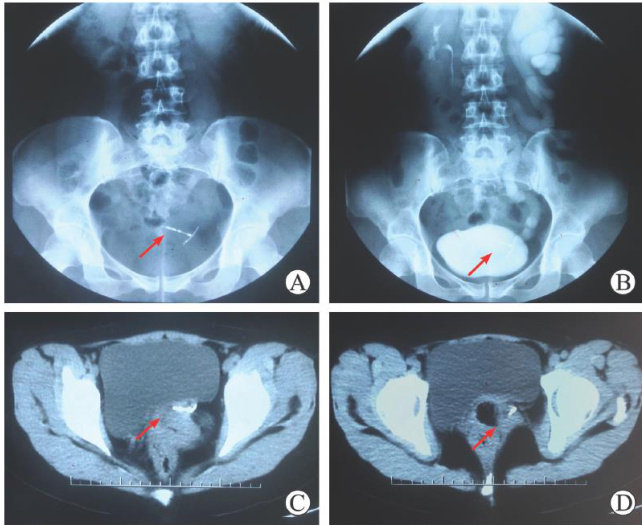

ABSTRACT:ObjectiveTo explore the diagnosis and treatmentof ureterovaginal fistula caused by intrauterine device (IUD)ectopia,soas to provide reference for the diagnosis and managementof this condition.MethodsAretrospective analysis was conductedonthesymptoms,signsexaminationresults,andtreatmentofapatient with ureterovaginalfistuladueto IUD ectopia.The relevant literature wasreviewed.ResultsThe 41-year-old female presented with vaginal urinary leakage for more thanl month.After admission ⋅ preoperative preparations were completed,and ureterovaginal fistula was confirmed with computed tomography(CT)and intravenous pyelography(IVP).After laparotomy was performed to remove the IUD, the patient was discharged after good recovery.Half a year after surgery,a telephonefollw-upshowed the patient had no subjective discomfort.Analysis of5reported casesof urinary leakage caused by IUDectopia revealed that the main cause was long-termchronic inflammatorystimulationbytheIUD.Among them,3cases werecured withsurgicalremovalof the IUDand fistula esection;of theother2cases,l refused surgical treatmentandlunderwent transvaginal fistula repair.Conclusion Ureterovaginalfistula caused byIUDectopia is ararecomplication.Earlydiagnosis requiresfamiliarity with itsetiologyand combinationof examinatios such asultrasound,IVP,and CT.Earlydiagnosis and treatmentcan prevent severecomplications.